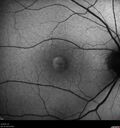

Pattern Dystrophy with Collapsed Vitelliform

74 year old female with vision loss in eye with collapsed vitelliform lesion.

Collapsed Vitelliform Pattern Dystrophy